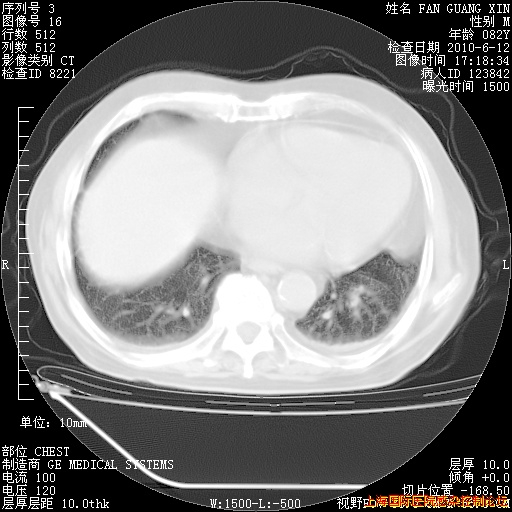

今天复查CT

今天CT

整整相隔30天的肺部CT好像有所好转啊。甲强龙减量第3天,需要观察体温。